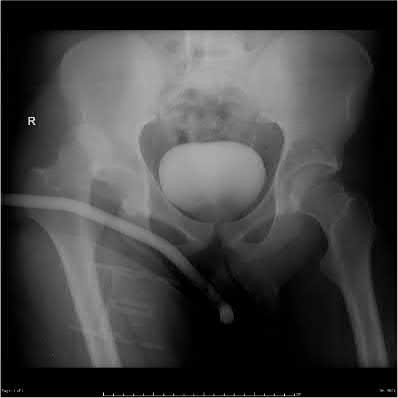

A 44-year-old male presents after being struck by a car. He is hypotensive, and has an obvious open tibia and a closed femoral shaft fracture. A pelvic radiograph is obtained and shown in Figure A. A representative CT scan image in shown in Figure B. The patient is placed in a pelvic binder, and his blood pressure normalizes with crystalloid and a blood transfusion. He then undergoes pelvic angiography, and his internal iliac artery is embolized. Which of the following definitive treatment options is most appropriate in this case?

The radiographs and CT scan show a fracture pattern consistent with an APC-III injury. This is most appropriately treated with pubic symphysis ORIF with a multi-hole plate and posterior iliosacral screw fixation.

APC-III pelvic ring injuries are associated with with disruption of the anterior and posterior SI ligaments (SI dislocation) as well as disruption of

sacrospinous and sacrotuberous ligaments. They are commonly associated with vascular injury and retroperitoneal bleeding.

Illustrations A, B, and C show the AP, outlet, and inlet postoperative radiographs.